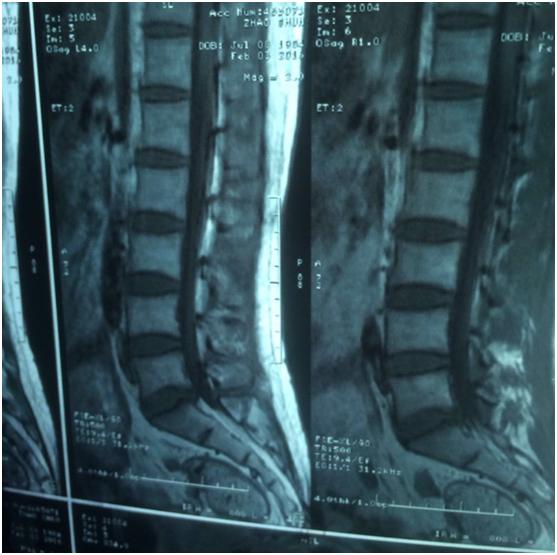

从患者的片子来看的话,虽然发的比较小,有的不太清楚,但是多数都能看清楚。从患者描述的症状来看的话,症状还是和轻度的椎间盘突出有关系。但是整个来说,压迫并不太重,而且患者症状也不是很重。